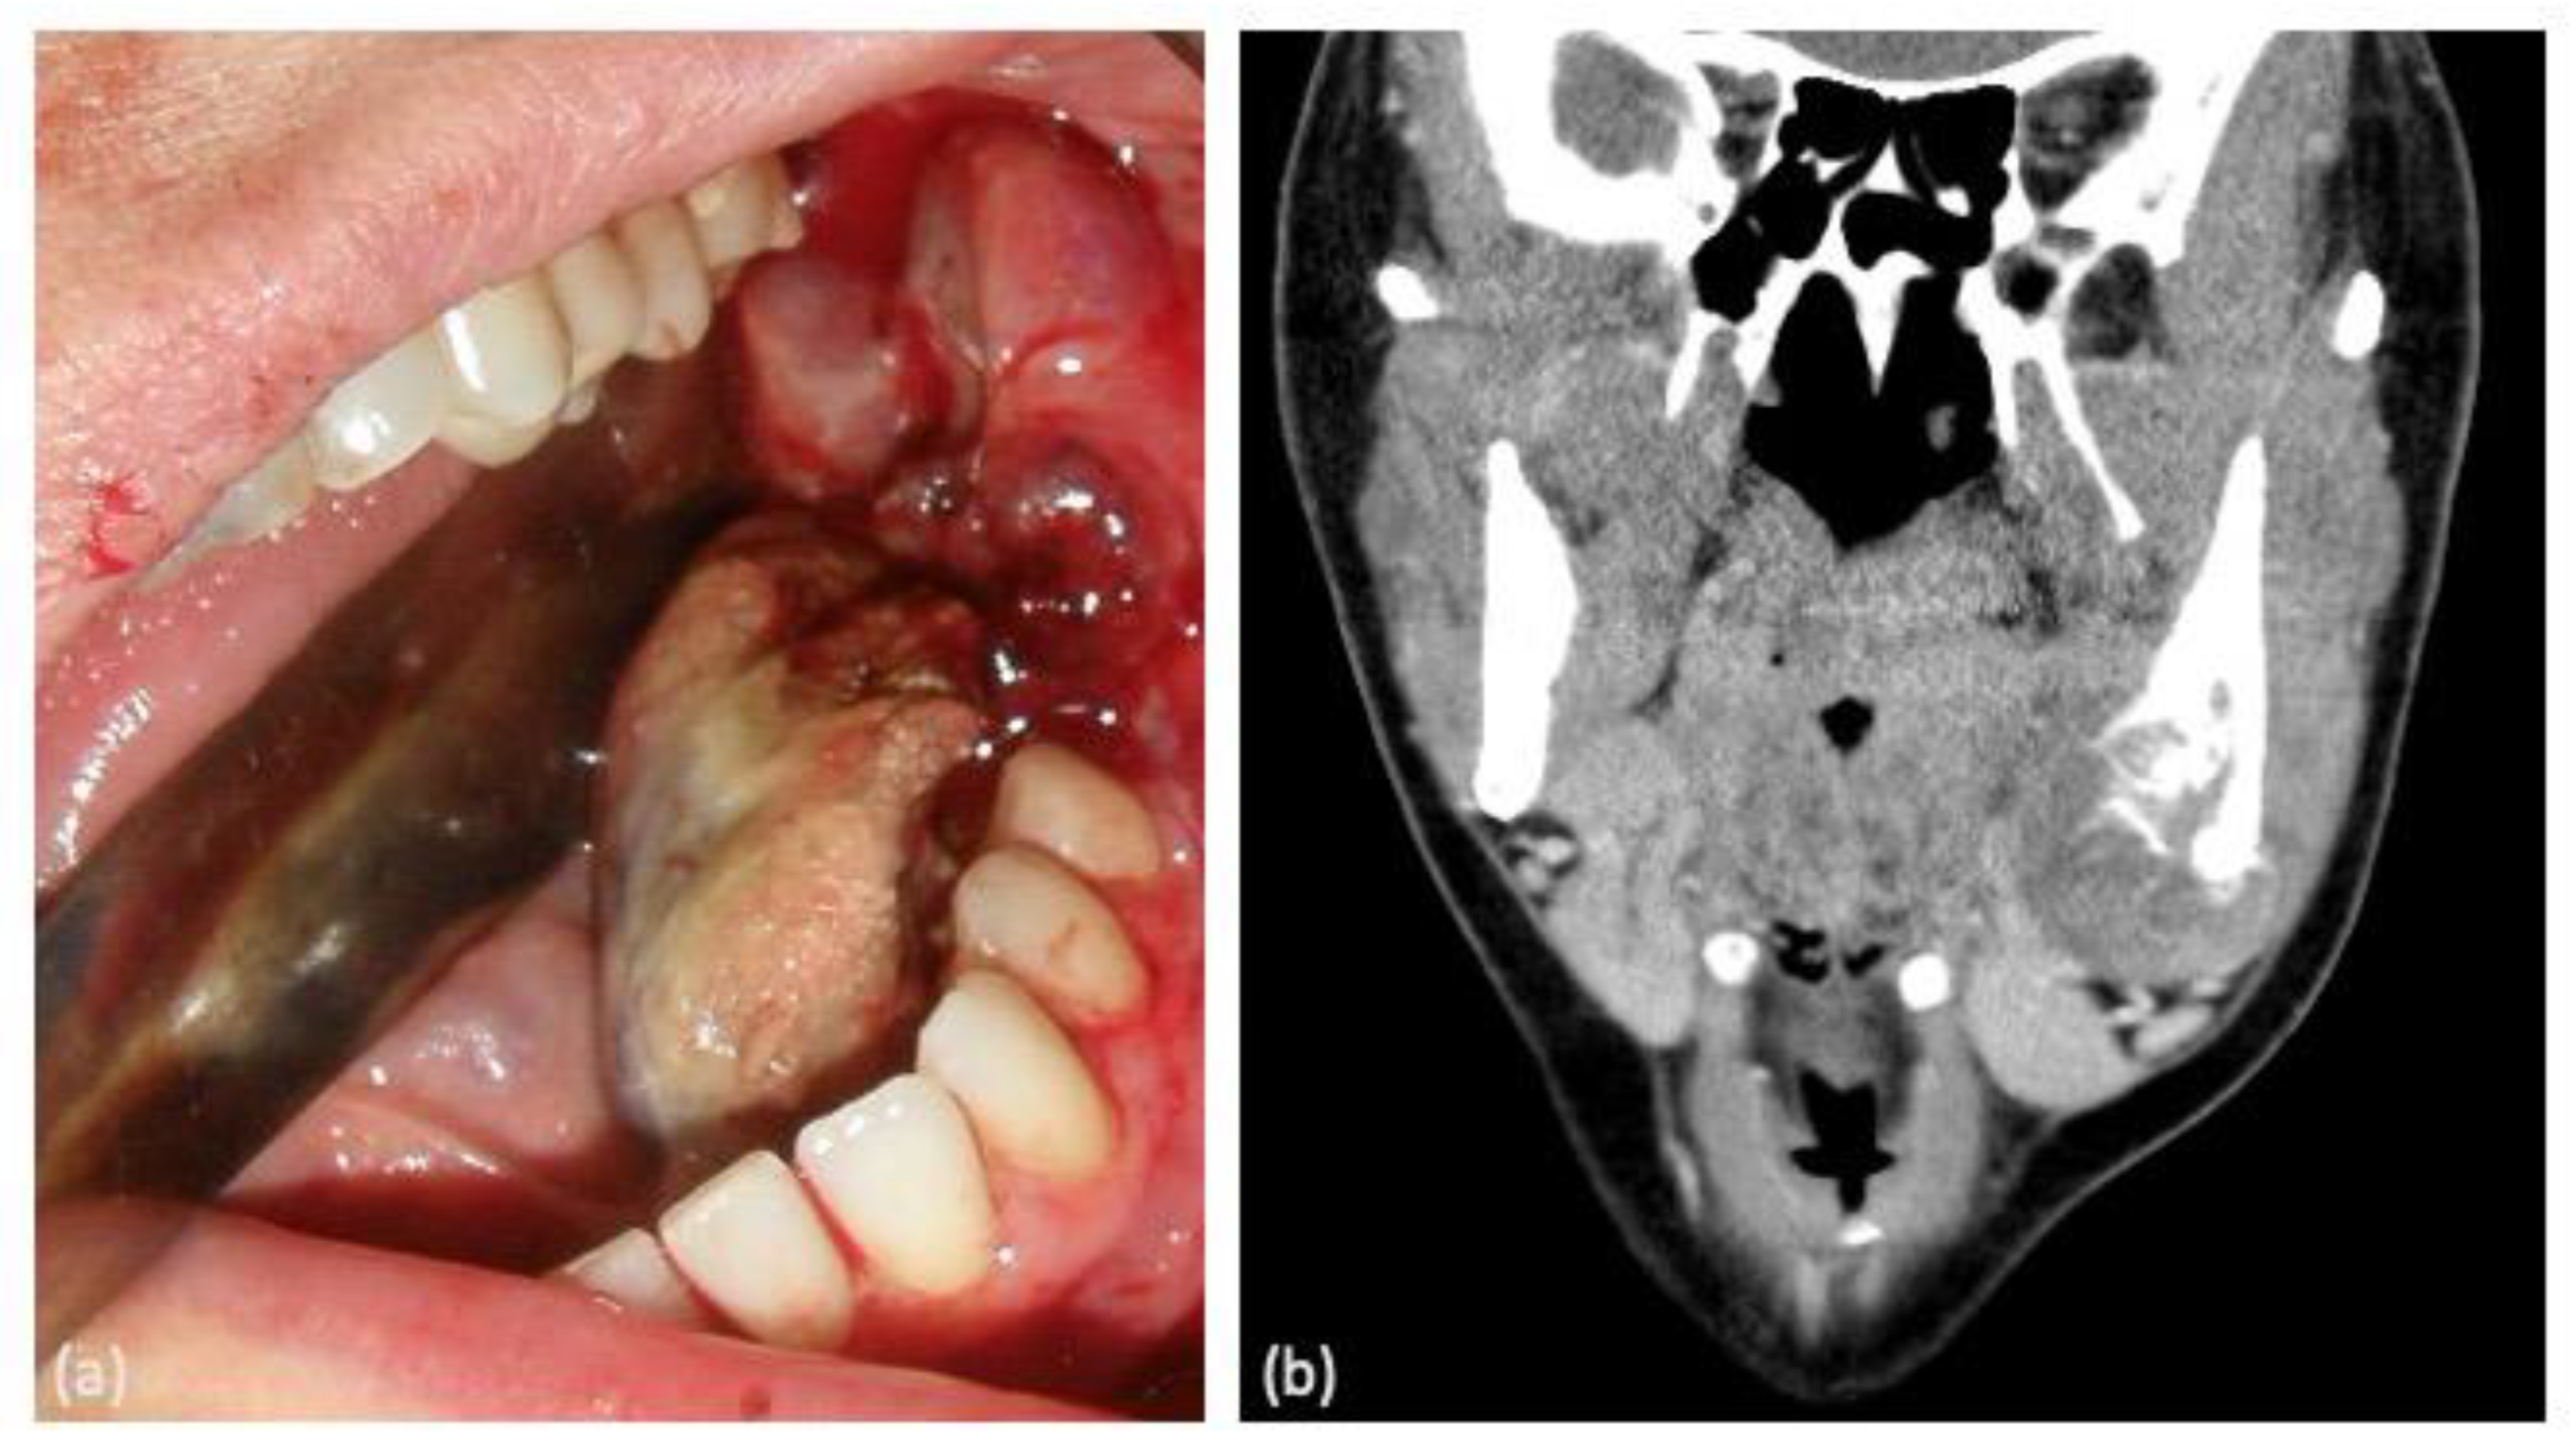

In terms of clinical manifestations of the tumor, painful inflammation was the most prevalent symptom (62.5%), either as a primary symptom or in association with other symptoms such as bleeding, dental mobility, and hypoesthesia of the inferior alveolar nerve. Notably, two cases presented with asymptomatic inflammation causing facial deformity (Figure 1).

Figure 1. (a) Intraoral clinical manifestation of the tumor in the left mandibular molar area showing bleeding. (b) Computed tomography coronal section image of the same lesion showing an area of osteolysis.